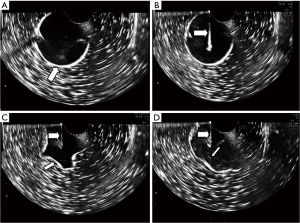

An empty box filled with coupling agent was regarded as the pelvic cavity. The coupling agent, at different concentrations, was used with physiological saline to simulate cysts of different viscosities. The blood viscosity of 5 mm2/s at 25 °C was selected as the highest viscosity, and this concentration was halved to generate the medium viscosity model. This resulted in coupling agent concentrations of 2.33% and 4.65%. After 24 hours, 50 mL of physiological saline, 2.33% coupling agent, and 4.65% coupling agent was filled into separate balloons. There were 30 balloons in each group, 15 in the experimental sub-group and 15 in the control sub-group. The equipment, phantom model, and cyst models are shown in Figure 1.

Contrast tests were applied to evaluate the application of the auxiliary device. In the experimental group, the auxiliary device was used, and in the control group, manual aspiration was performed using a syringe. The experimental and control groups were carried out by three people, the probe holder, the operator, and the assistant. The job of the probe holders was to support the probe.

In the control group, the pelvic cyst models were placed in the assistant's puncture groove, and the operator quickly punctured the pelvic cyst model under the guidance of ultrasound. The needle was connected to a 30 mL syringe to aspirate the fluid inside the cyst model; then, the cyst wall was washed with 60 mL physiological saline. The assistant was responsible for the transmission of physiological saline.

In the experimental group, the pelvic cyst models were also placed in the assistant’s puncture groove, and 60 mL physiological saline was injected into the bag. The assistant adjusted the pressure of the infusion pressure bag and the negative pressure attractor. The operator then connected the puncture needle to the auxiliary device and quickly punctured the pelvic cyst model. The cyst fluid was aspirated with a negative pressure of 0.08 MPa. Due to the cysts’ deformation during aspiration, the puncture needle’s position was adjusted appropriately to avoid the destruction of the cyst wall. When there was about 5–10 mL cyst fluid remaining, the operator adjusted the three-way valve and infused the cyst model with physiological saline. The infusion pressure was controlled at 140–160 mmHg. The above suction was repeated until the physiological saline was depleted. The time of aspiration, time of fluid injection, the washing time, and the operation time were recorded. The steps involved in the whole procedure are shown in Figure 2.